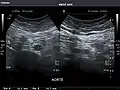

Kidneys: Right and left kidneys measure 11.5 cm and 12 cm in length respectively. No hydronephrosis. Small left lower pole kidney cyst.

Right kidney